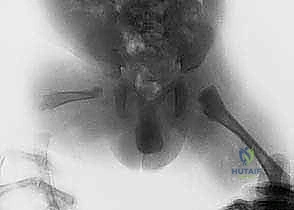

2. قطع عظم ديجا (Dega Osteotomy)

في الحالات التي يكون فيها الحق (تويج الحوض) ضحلاً ولا يغطي رأس الفخذ بشكل كافٍ (Hip Dysplasia)، يجري الدكتور هطيف عملية "ديجا". يتم فيها عمل شق في عظام الحوض وثنيه للأسفل لتكوين سقف متين يغطي رأس الفخذ، ثم يتم وضع طعم عظمي لتثبيت الوضع الجديد. هذا الإجراء ضروري لمنع خلع الورك أثناء عملية التطويل اللاحقة.

معرض الصور السريرية لمراحل التثبيت والتطويل:

معرض إضافي لصور الأشعة والمتابعة الدقيقة للحالات: